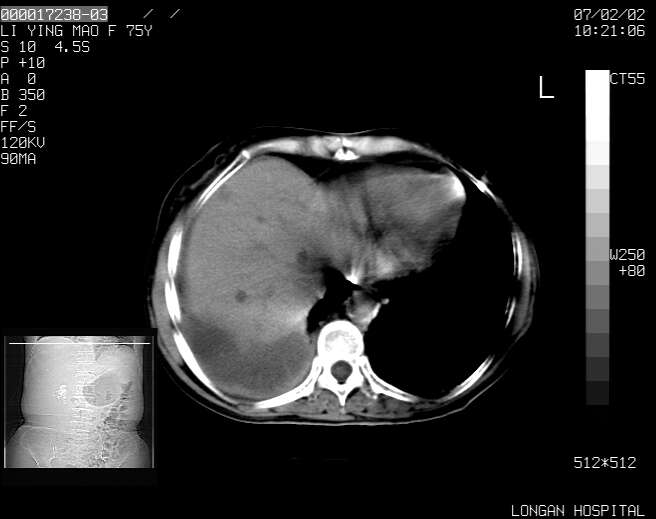

以下是引用dyqct在2007-2-10 8:53:00的发言:[br]考虑:1、肝脏多发囊肿[br] 2、左肾囊肿,右肾多发结石并积水。[br] 3、右胸少量积液。[br] 4、右肾周包裹性积液或淋巴管瘤(有见缝就钻的征象、薄隔、小结节状钙化)?[br] 5、腰椎动脉瘤样骨囊肿?[br] [br] [br]